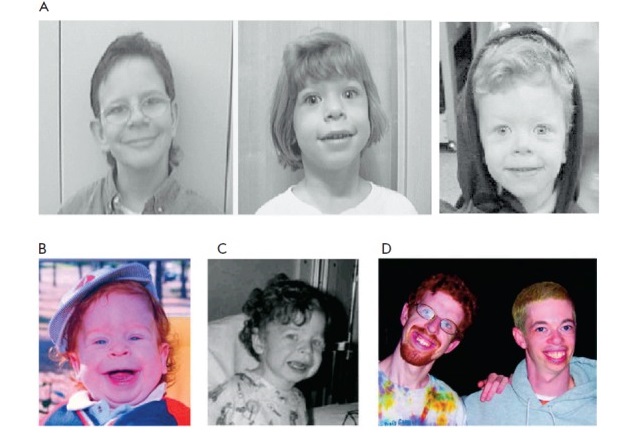

14- Síndrome de William

El síndrome William se caracteriza por la pérdida de material genético en el cromosoma 7, también llamado monosomía.

Esta patología se caracteriza por alteraciones faciales atípicas, problemas cardiovasculares, retraso cognitivo, problemas de aprendizaje, etc.